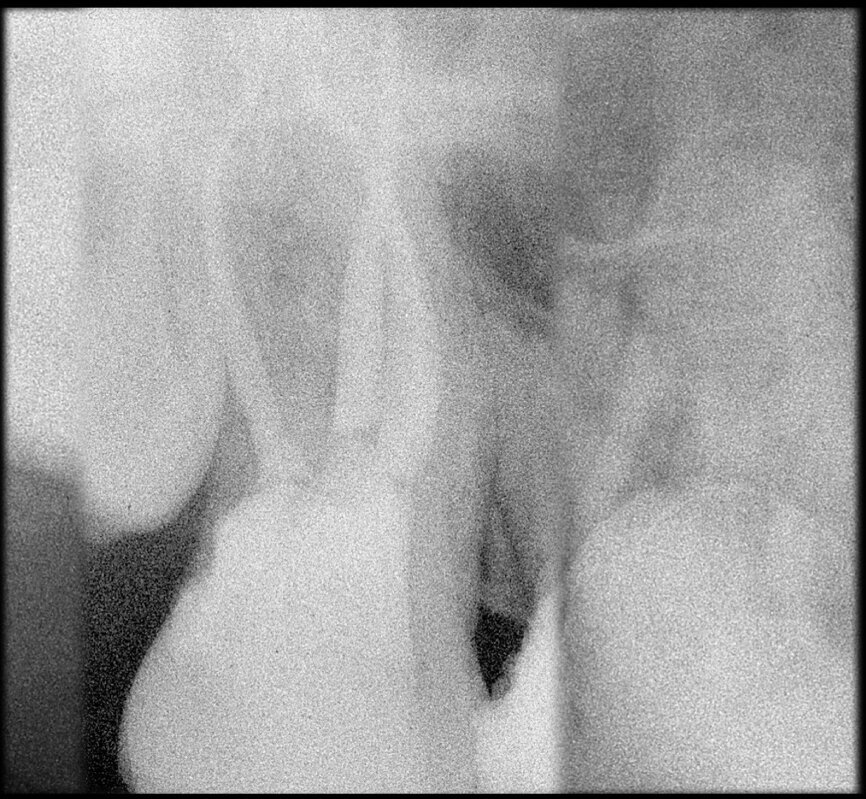

Preoperative CBCT evaluation is useful in cases requiring a surgical approach, not only in order to confirm the presence of a lesion but also to plan the procedure and, in particular, identify the type of surgical incision to be used, based on its size and location (Figs. 23–25). This specific case is characteristic of this situation. The intraoral radiograph did not make it possible to ascertain the extent of the lesion, which involved not only the apical region of the premolar but also a distal edentulous segment. This region would need to be treated with regenerative therapy in order to guarantee correct healing of the area, with subsequent insertion of a membrane, the flap must be protected using a totally different approach to that required for endodontic surgery. The intraoperative images illustrate the various stages of the procedure (Figs. 26–28). The CBCT scan performed 12 months later confirmed complete healing of the apical lesion and perfect graft integration (Figs. 29–31).